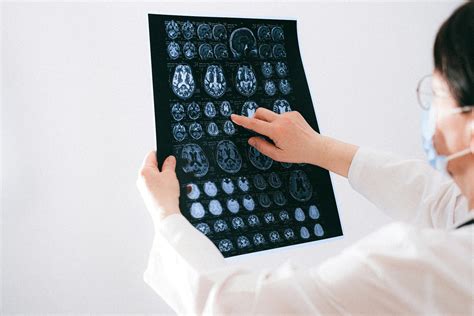

The Role of ADHD Brain Scan in Diagnosis

Traditional methods of diagnosing ADHD rely heavily on behavioral observations and self-reported symptoms. However, these methods can be subjective and prone to bias. ADHD brain scan technology offers a more objective approach by providing visual and quantitative data on brain structure and function. This can help clinicians make more accurate diagnoses and tailor treatments to individual needs.

Improved Diagnosis

By providing objective data on brain structure and function, ADHD brain scan technology can enhance the accuracy of ADHD diagnosis. This is particularly important for individuals whose symptoms may overlap with other conditions, making diagnosis challenging.